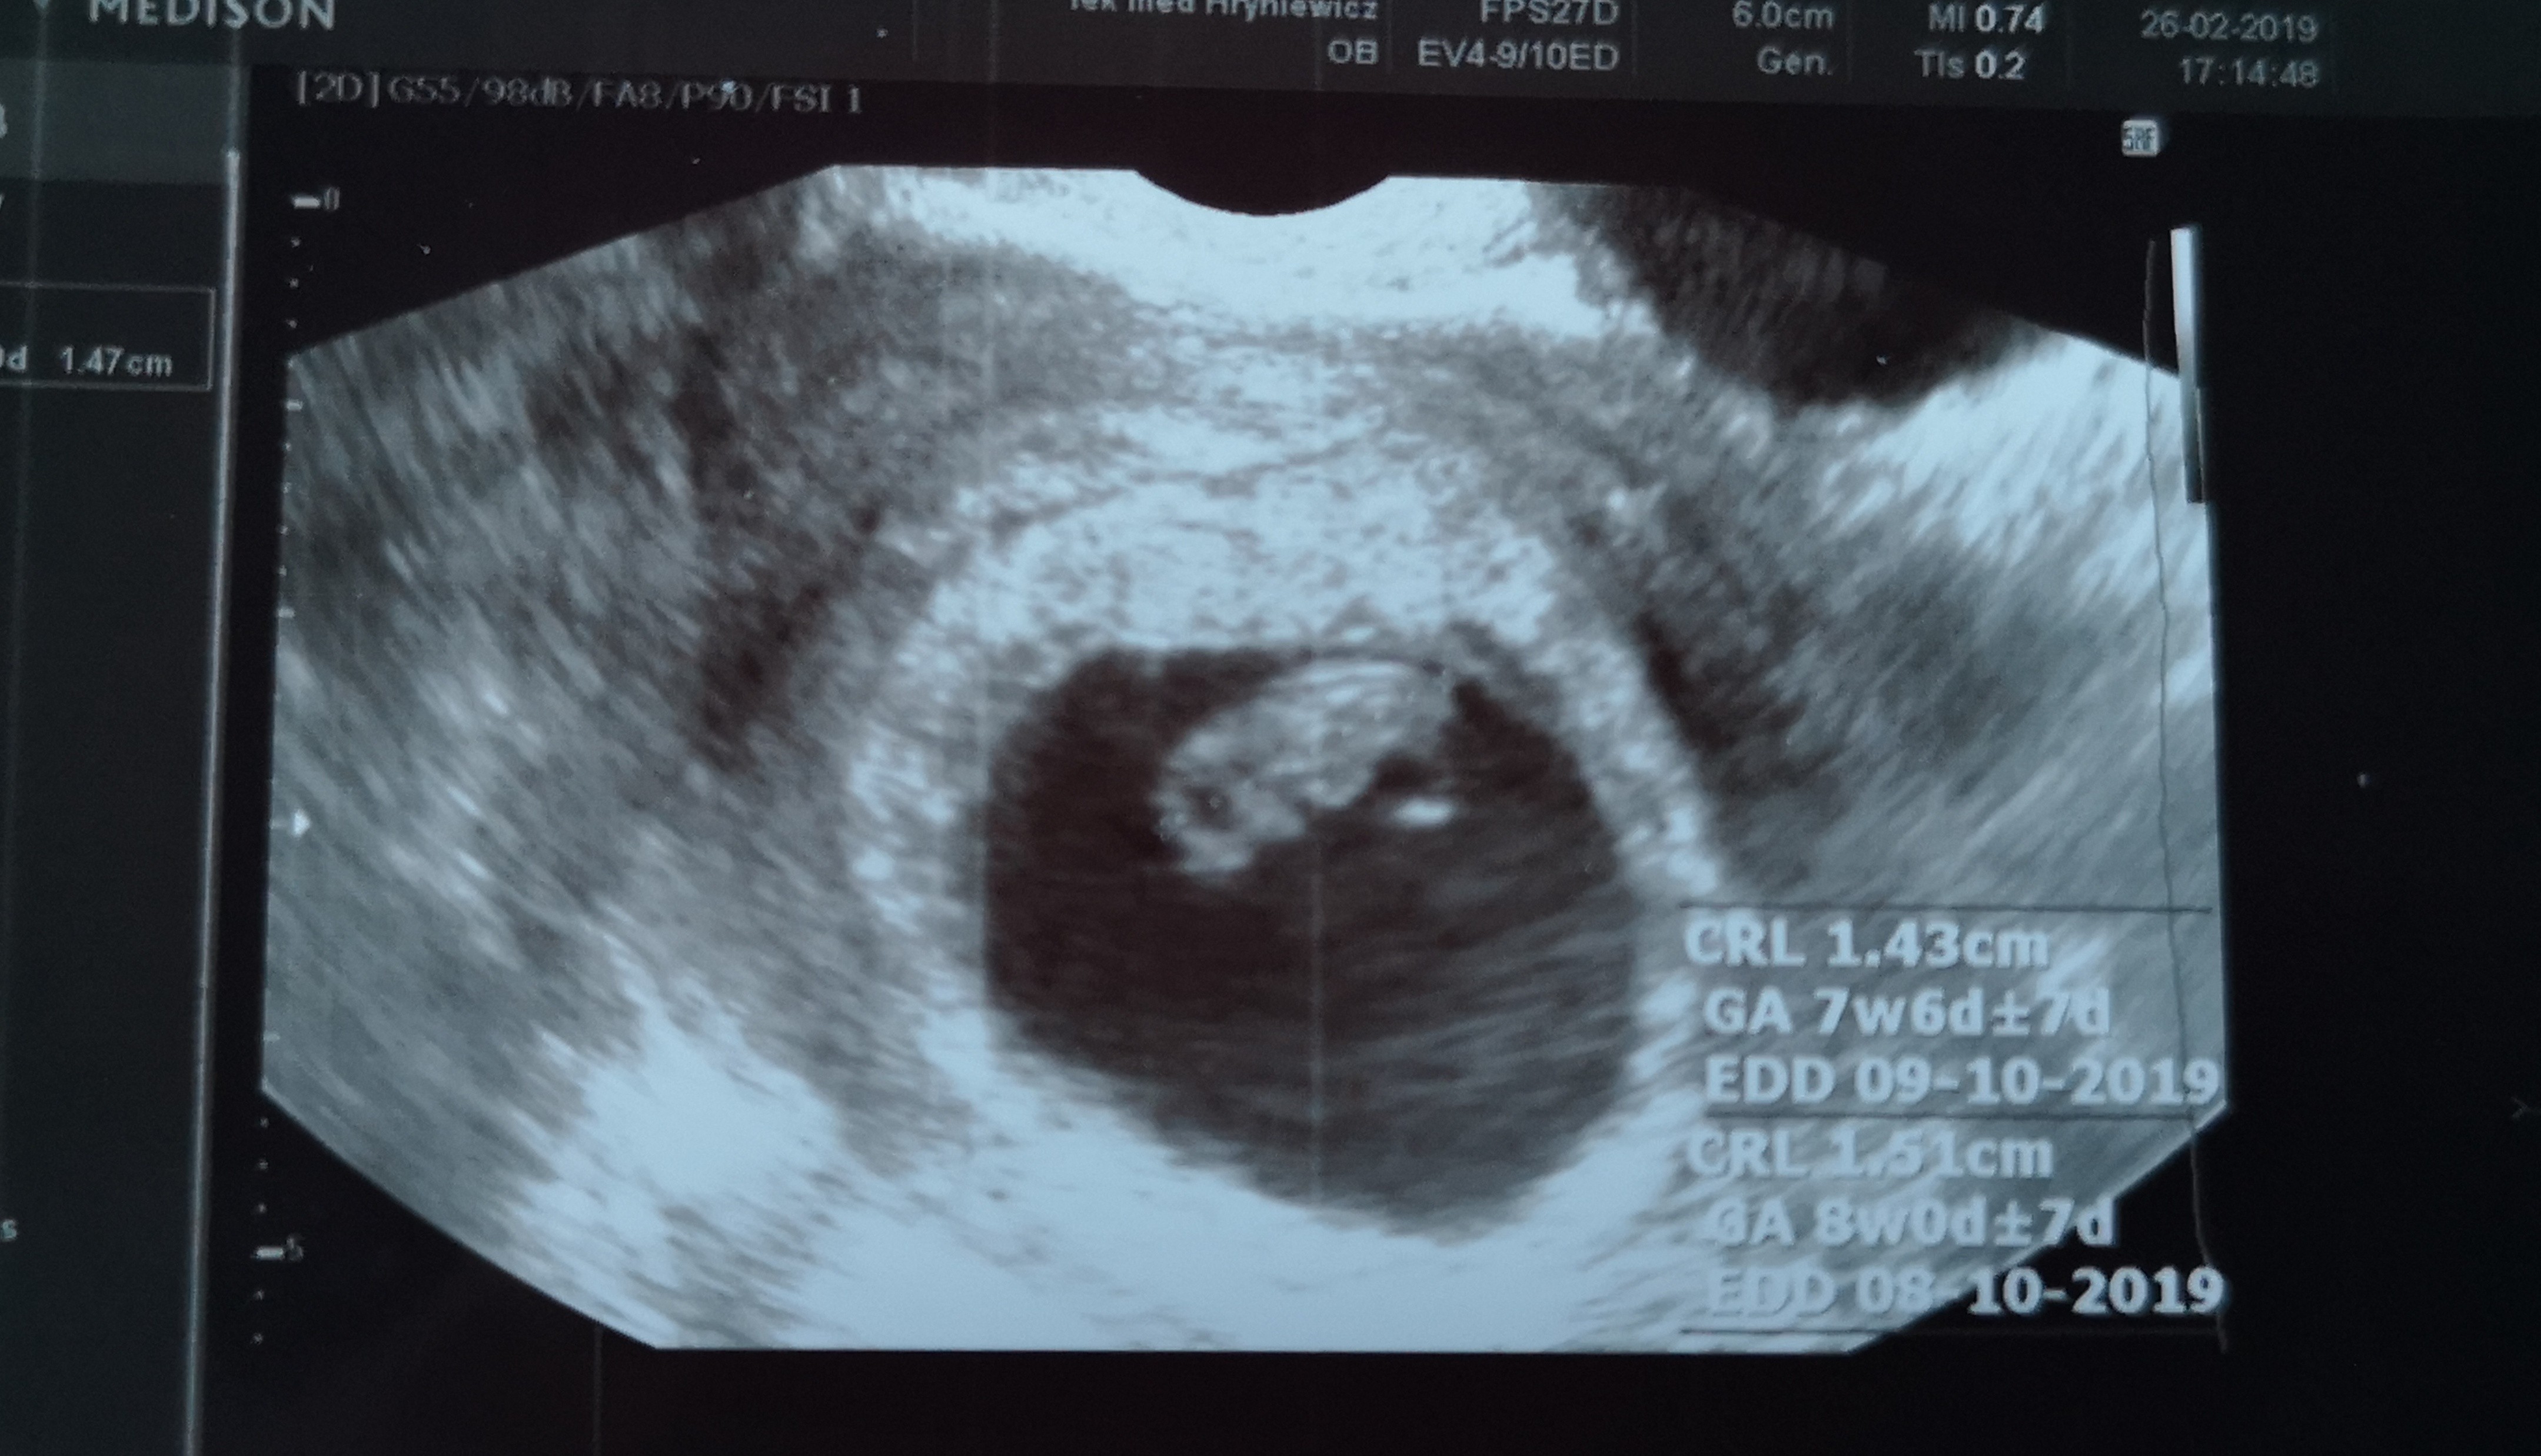

Siemanko :) 1,5 cm człowieka z bijacym serduszkiem :) lista badań do zrobienia. Karta założona, kolejna wizyta za 3 tygodnie :) niestety rower musi zaczekać do czasu kiedy młody człowiek opuści brzusio.

Termin przwskoczyl z 2 na 8/9.10 :)

IMG_20190226_171300-01.jpeg